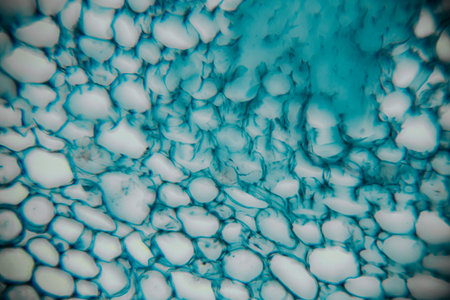

High-resolution...